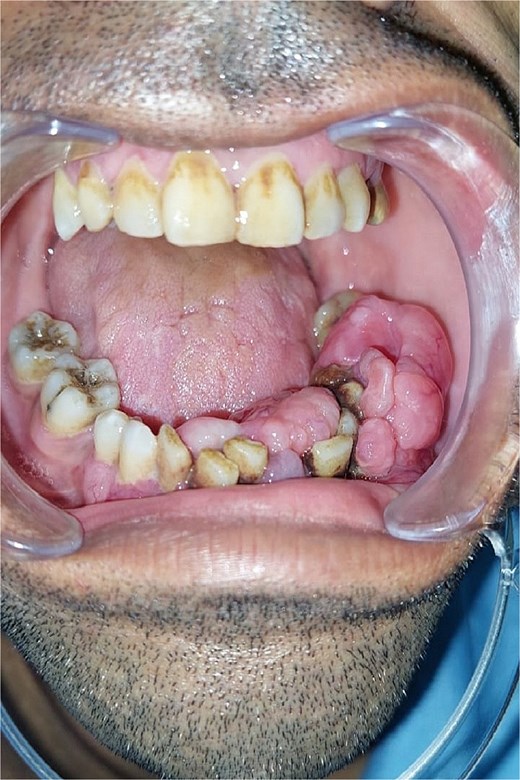

Clinical examination revealed a moderately painful, non-bleeding mass from teeth 37 to 44, with mobility of the incisivocanine complex and hypoesthesia in the left labiomental area. The lesion was localized, with no infection or acute inflammation signs (Fig. 1).

Pre-operative image showing the intraoral appearance of the leiomyosarcoma with gingival hypertrophy.